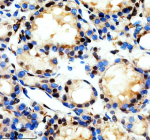

Immunohistochemical staining of REST using anti-REST antibody. REST was detected in a paraffin-embedded section of human colon cancer tissue. Heat mediated antigen retrieval was performed in EDTA buffer (pH 8.0, epitope retrieval solution). The tissue section was blocked with 10% goat serum. The tissue section was then incubated with 2 ug/ml rabbit anti-REST antibody overnight at 4oC. Peroxidase Conjugated Goat Anti-rabbit IgG was used as secondary antibody and incubated for 30 minutes at 37oC. The tissue section was developed using an HRP secondary and DAB substrate.